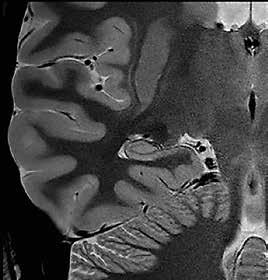

Ziel der Forschungen an der Universität Bordeaux war die hochaufgelöste und detailreiche Darstellung spezieller Hirnareale, wie des Hippocampus oder des Claustrum. Diese Regionen hatte Prof. Tourdias schon am 7T-System bei seinem Aufenthalt an der Stanford-Universität studiert. Nun war es mit der AiCE-Technologie möglich, vergleichbar aufgelöste Bilder auch bei 3T in akzeptabler Untersuchungszeit zu erzeugen (siehe Abb. 5 a und b).

Natürlich lassen sich die Vorteile einer höheren Auflösung nicht nur in der klinischen Forschung nutzen, sondern sind auch dazu geeignet, bei-

Abb. 5 a + b: Hochaufgelöstes Bild des Hippocampus; 0,15 mm x 0,15 mm; 2 mm Schichtdicke; rechts mit AiCE-Rekonstruktion. Mit freundlicher Genehmigung des Unversitätsklinikums Bordeaux. Abb. 6 a + b: Hochaufgelöstes Bild des Knies; 0,15 mm x 0,15 mm (interpoliert); 1 mm Schichtdicke; rechts mit AiCE-Rekonstruktion.

42 // VISIONS 31

spielsweise einen Knorpelschaden im Knie im Detail zu zeigen.